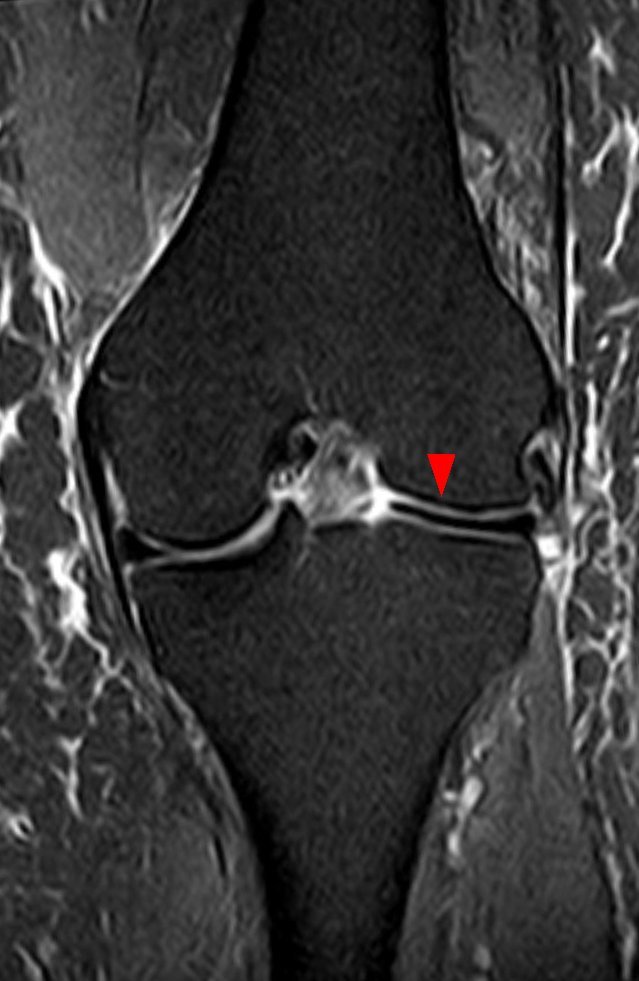

원반형 반월판(Discoid meniscus)이 인구의 3% 정도로 발생하는 흔한 변이에 해당하는데, 반월판의 형태학적인 거대화로 나타난다. (그림 46-7) 환자는 대개 무릎을 신전하고 굴곡할 때 염발음을 나타낸다. 이는 관상면 상에서 최적으로 진단되고 시상면 상에서는 그렇지 않은데, 기술상의 다양함이 나타날 수 있다. 대퇴외과의 중간 레벨을 관통한 관상면 MRI 영상에서 대퇴외과의 중간 포인트 아래로 가운데 부위로 이어지는 반월판이 원반형 반월판(discoid meniscus)으로 불린다.

△ 그림 46-7. 외측 원반형 반월판

중간 대퇴외과 레벨을 통과하는 관상면 T1 강조 시퀀스는 외측 원반형 반월판으로 나타나는 외측 반월판이 외측 대퇴외과의 중간 포인트 아래 가운데 부위로 연장됨을 보여준다. (화살표) 정상적인 내측 반월판은 내측 대퇴내과로 이어짐은 보이지 않는다. M = 내측, L = 외측